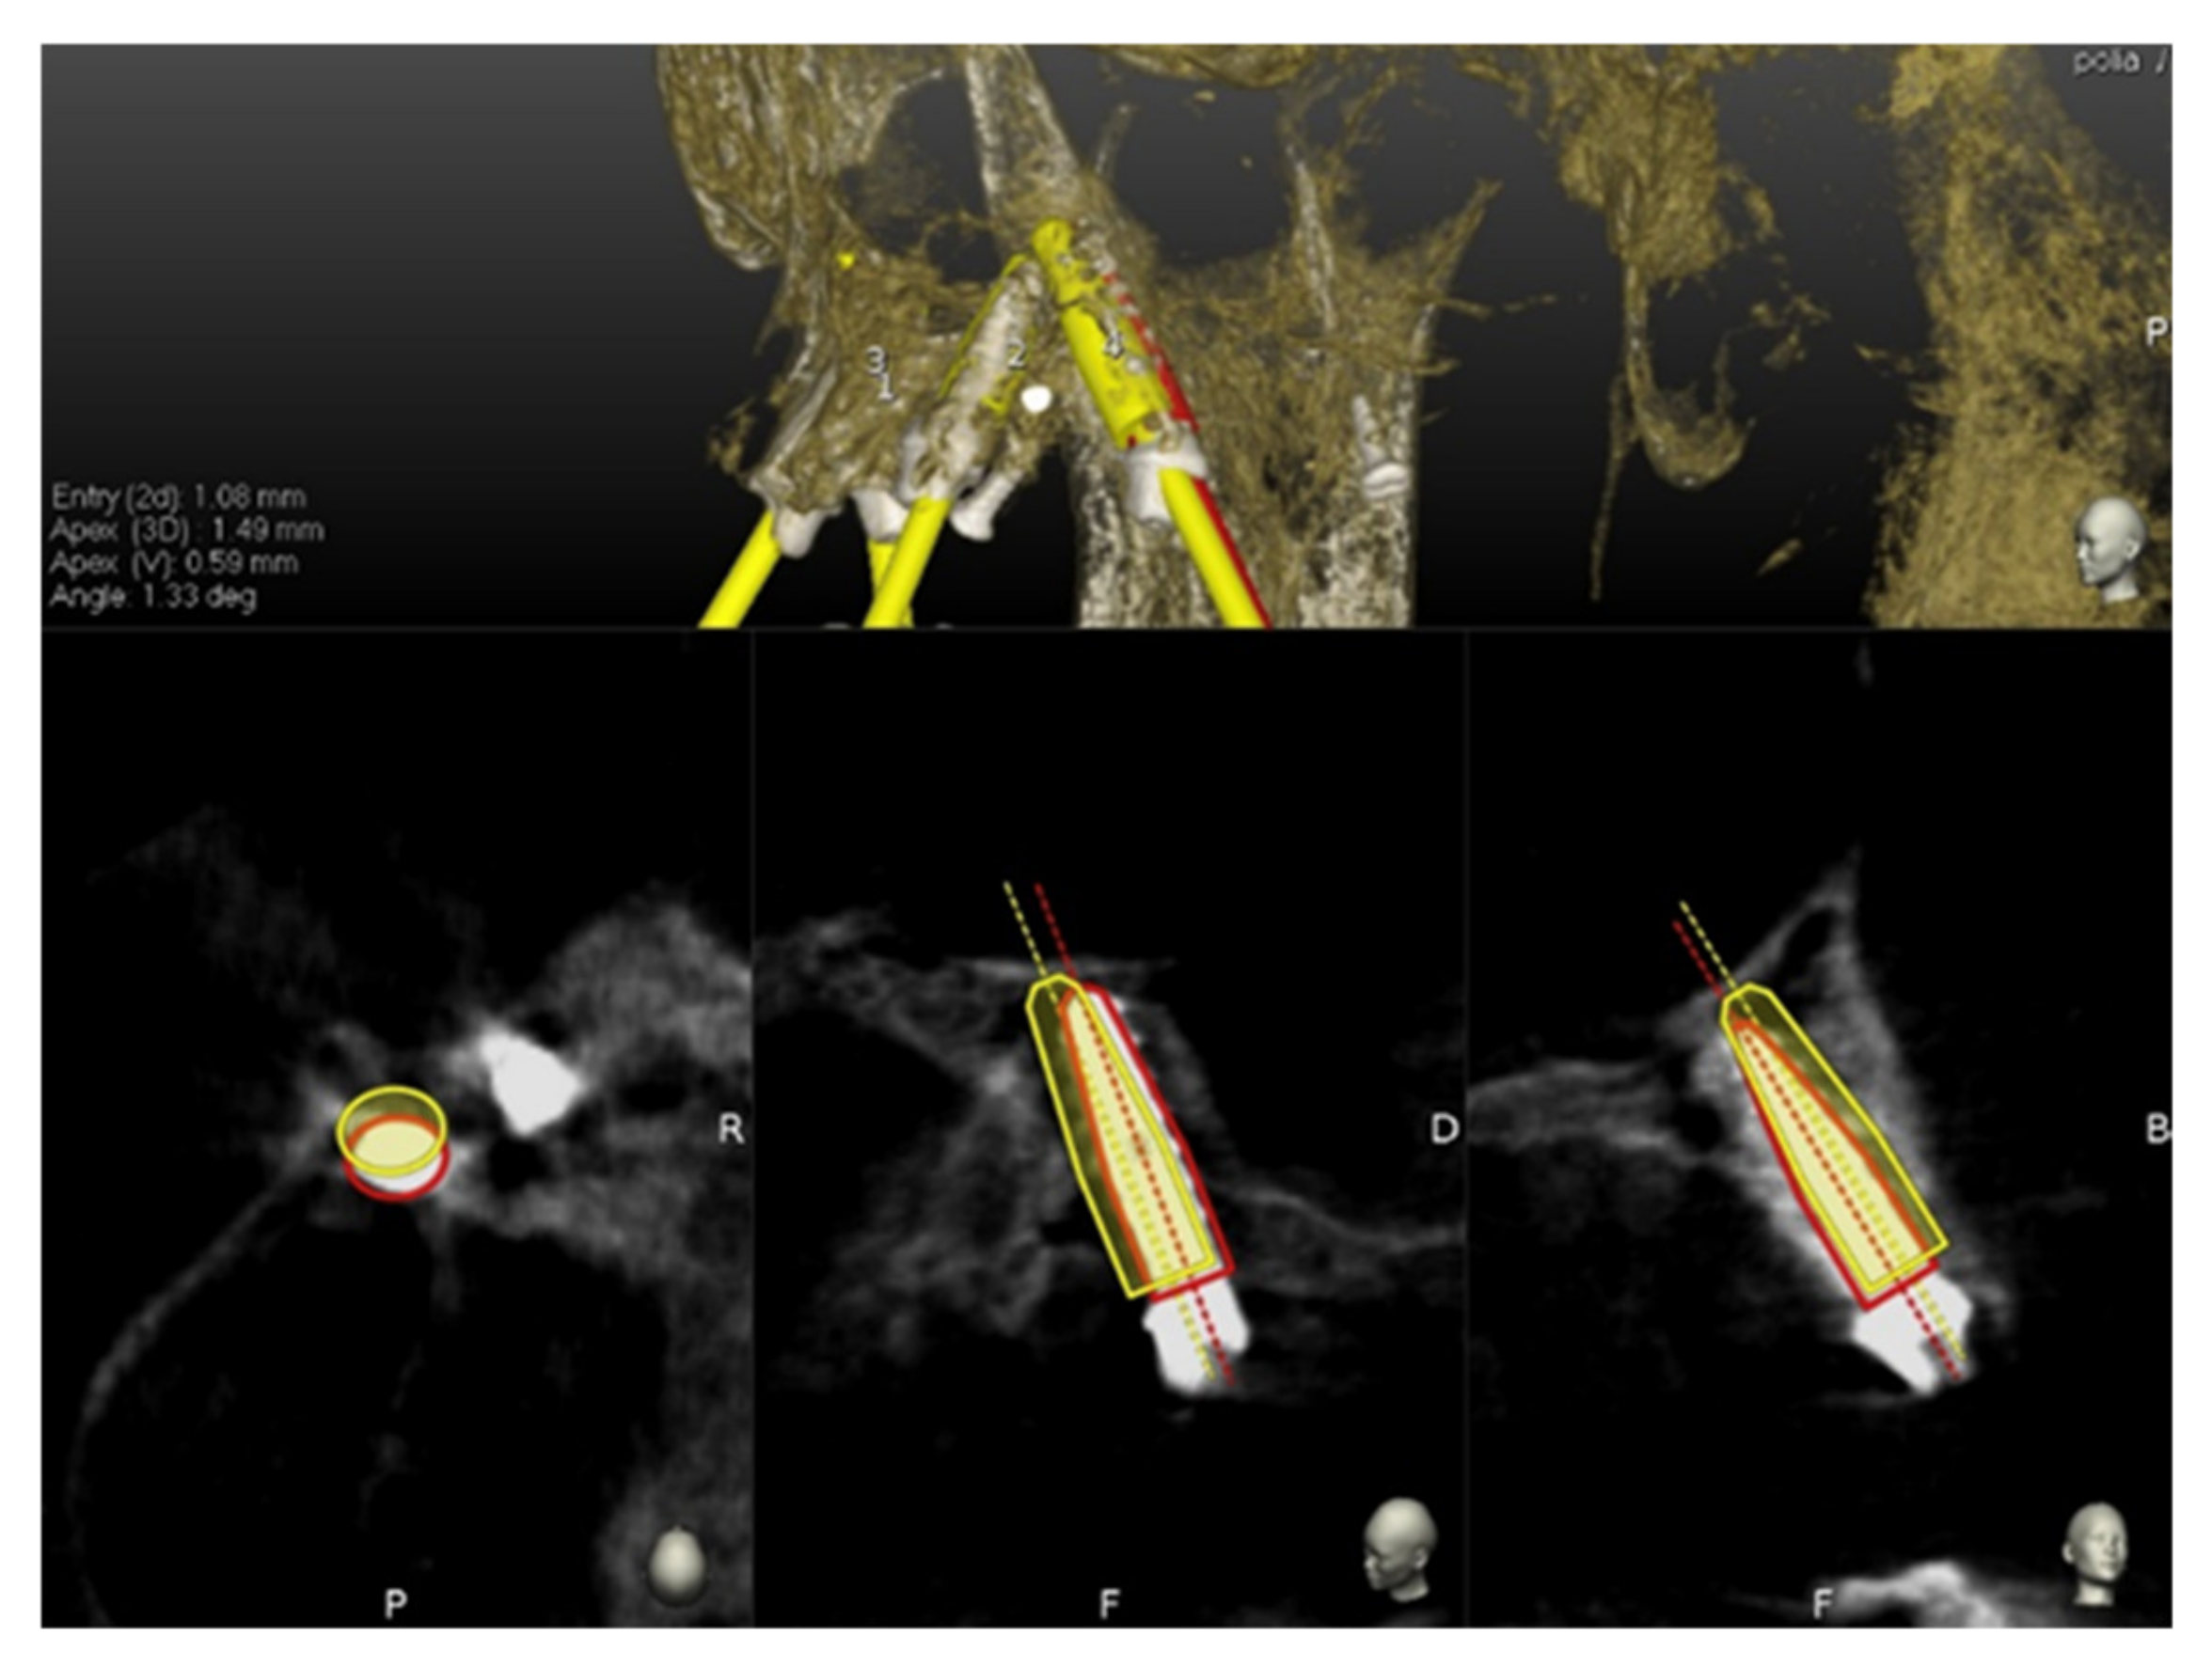

The handpiece drill axis and drill tip are calibrated, and a second verification of the accuracy is carried out in the same manner as the tracer. Once the drill axis and drill tip accuracy are verified, the navigated implant placement can be carried out following the target view, which allows the clinician to verify, in real time, the entry point, depth, and angulation of the planned osteotomy as related to the plan. The other views that the clinician can see on the screen enable him/her to follow the position of the drill during the osteotomy in the coronal and sagittal views (Figure 5).

The preoperative surgical plan and the postoperative CBCT were superimposed using an accuracy evaluation application (EvaluNav) provided through the Navident navigation system (Claronav Inc., Toronto, ON, Canada). The registration was done directly between the two volumetric images. The software provides various visualization tools which confirm the two images are precisely aligned and improve the accuracy if the alignment is less than ideal. Once the user is satisfied with the volumetric registration, the software automatically fits a model of the implant to its appearance in the post-operative image and computes the angular axis corrected between the planned and actual implant locations (Figure 8).

Figure 5. The figure indicates the several views on the screen during surgery and the advancing of the drill into the bone. (a) Tracker video stream, (b) panoramic view, (c) mesiodistal section view, (d) Bucco-lingual section view, (e) depth indicator, and (f) target view.

Figure 8. The software automatically fits a model of the implant to its appearance in the post-operative image and computes the angular axis corrected between the planned and actual implant locations (implant inserted with dynamic guidance).